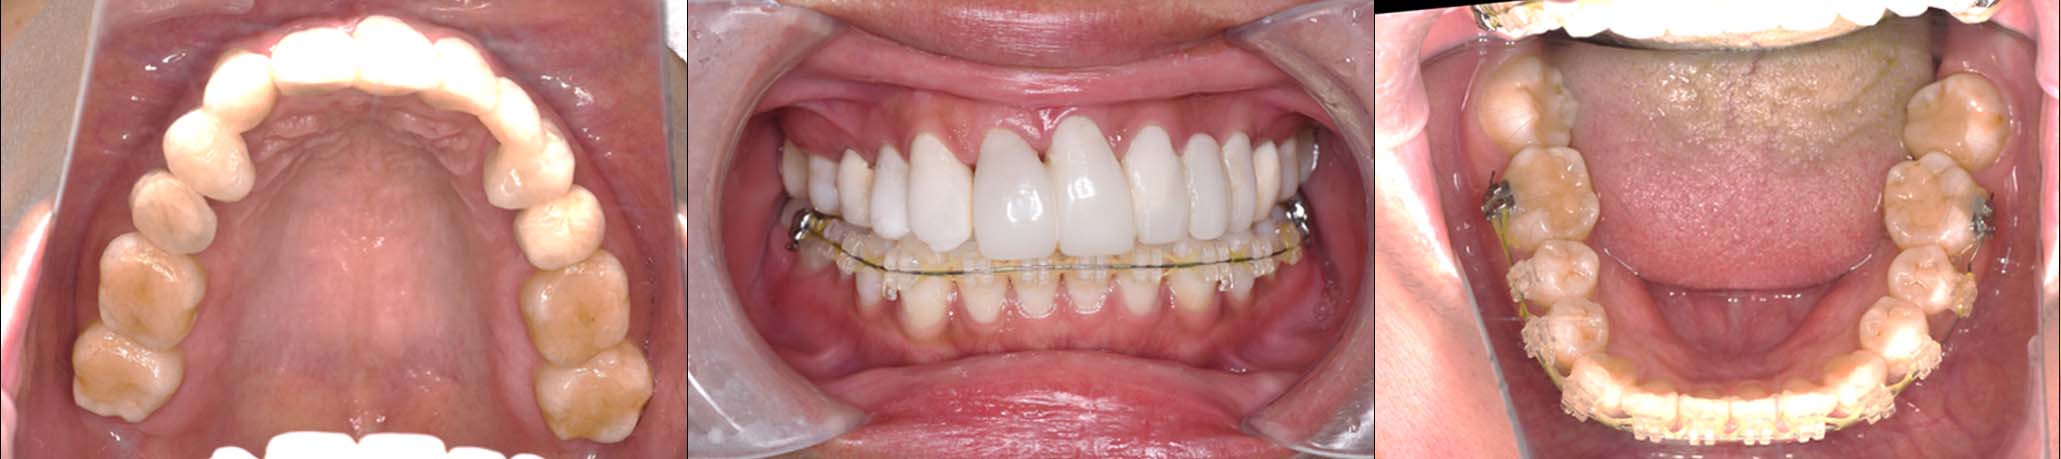

| 治療内容 | ①スプリントを装着 ②副子を装着 ③2024年4月 口腔内反映開始 ④副子を入れた状態の所まで咬合を挙上 (バイトアップ) ⑤2024年5月 上顎前歯部8本へ仮歯(TEK) を装着 |

バイトアップ後